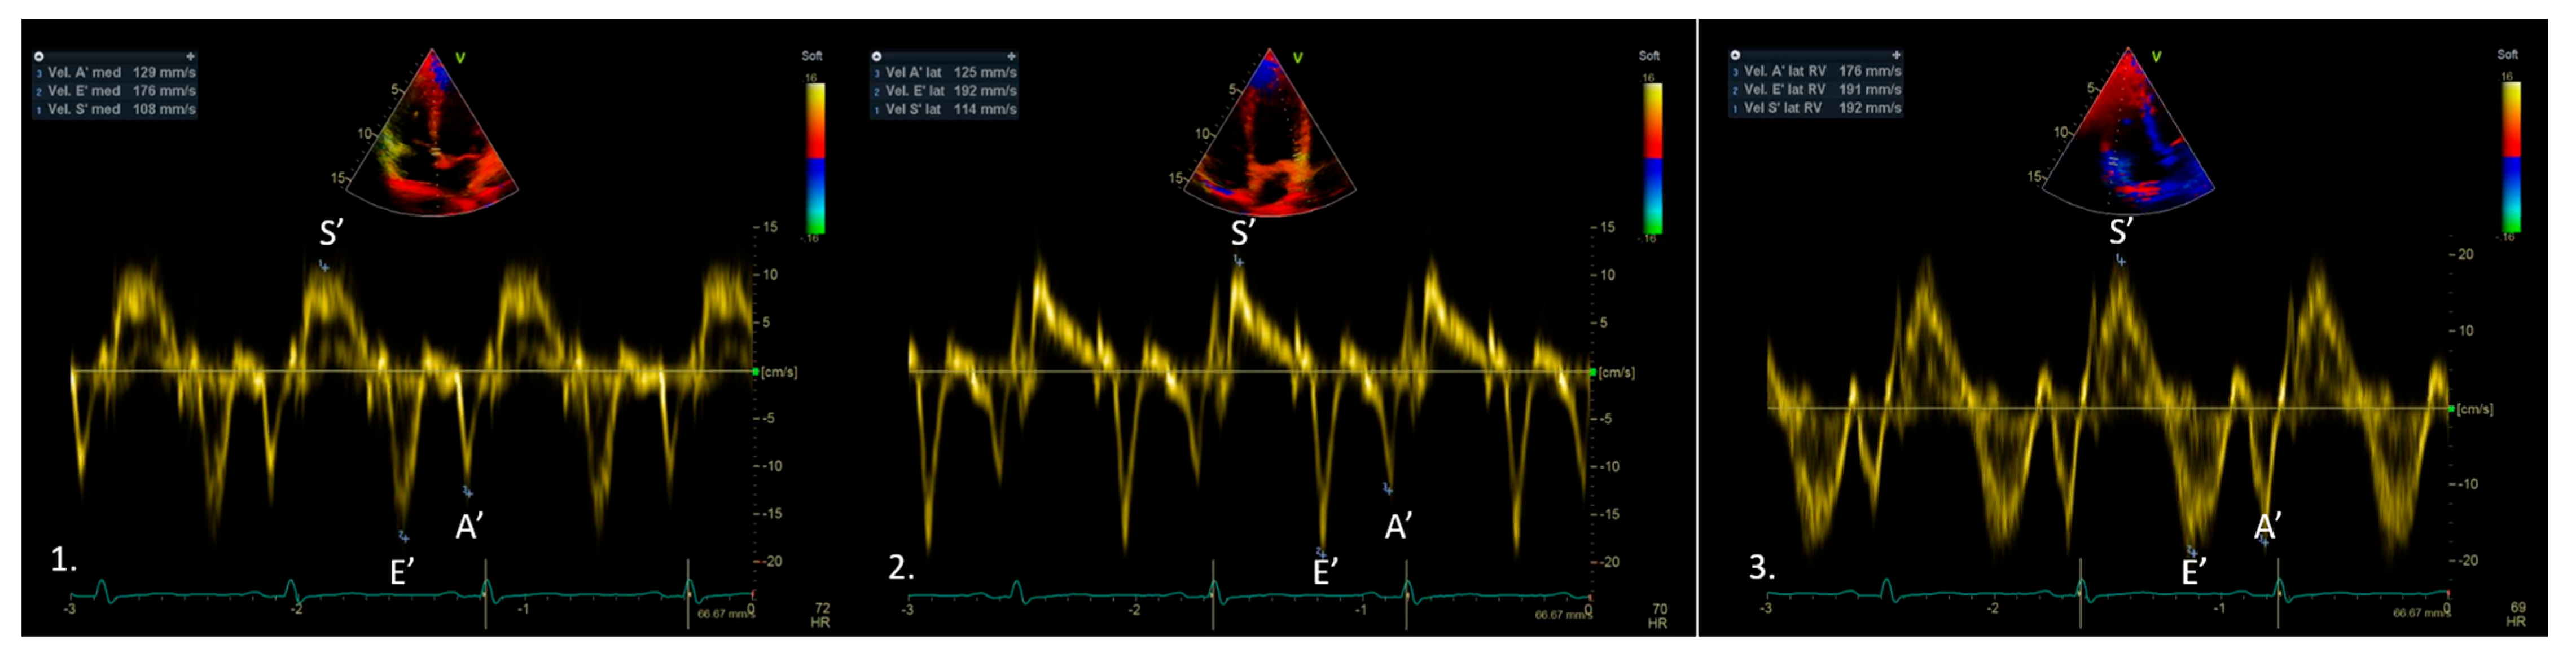

3. Tissue Doppler Imaging Characteristics